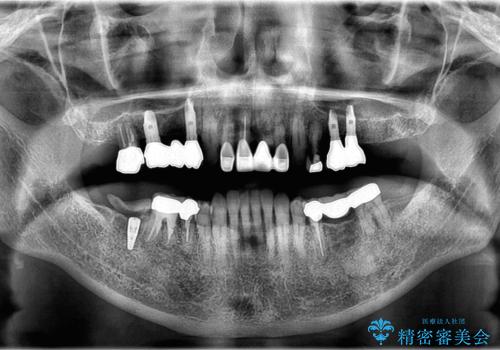

- 「他院で治療した被せ物が外れた」を主訴に来院された患者様です。診査診断を行い歯の保存が困難だったため抜歯後、インプラントで治療しました。

インプラントを入れるためには十分な骨の高さと幅が必要です。術前に検査を行い必要であれば別途、骨や角化歯肉を増やす治療も行う事があります。

インプラントの土台と被せ物は適合が良い物を制作するため、シリコン印象材を使用し型を取っています。